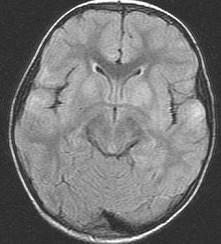

女,3岁,头痛、呕吐1周,请结合MRI图像,选择最可能的诊断是()A.脑膜炎B.硬膜下出血C.脑转移瘤D.脑梗死E.脑脓肿

问题 女,3岁,头痛、呕吐1周,请结合MRI图像,选择最可能的诊断是()

选项 A.脑膜炎 B.硬膜下出血 C.脑转移瘤 D.脑梗死 E.脑脓肿

答案 A